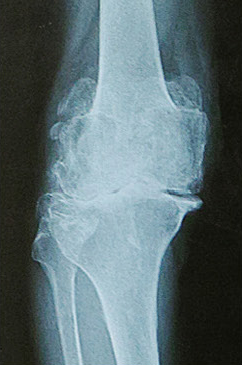

東京大学のROADスタディという疫学調査によると、レントゲン上では50代以上の2,400万人がこの変形性膝関節症の所見を有しているといわれています。このうち、実際に痛みを伴っている方は820万人という結果も出ています。

変形性膝関節症の

レントゲン